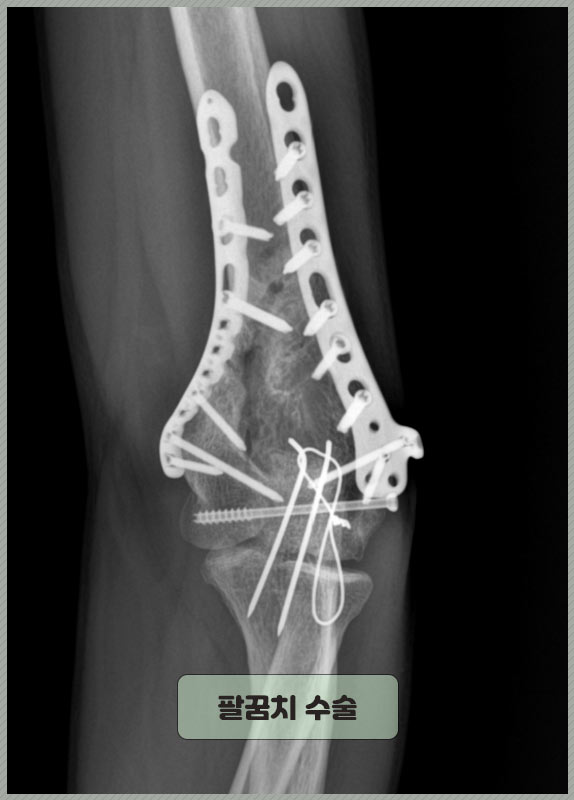

▶▶▷ 40대 후반 김 ** 님(경기) 사례자분은 운동 중에 다치셨고, 팔꿈치 골절 진단을 받으셨습니다. 정확한 진단명은 다음과 같으며 위팔뼈인 상완골 아랫부분이 손상되었습니다. Lt. distal humerus intraarticular comm. fx. 좌측 원위부 상완골 관절 내 분쇄 골절 뼈가 세 조각 이상 조각나듯 부러지고 부러진 부분이 팔꿈치 관절안까지 침범한 상태였습니다. 따라서 수술 치료를 시행 받으셨어요. 금속판, 나사 핀 등을 이용해 뼛조각을 정밀하게 고정했습니다.